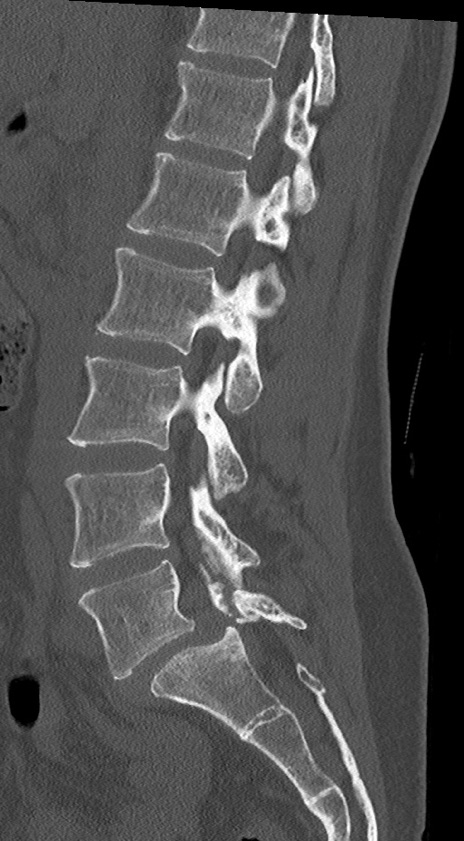

【整形】TIPS症例4 腰椎CT(矢状断像)

腰椎CT

横断像